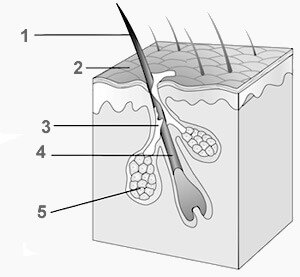

Este grupo de glándulas se caracteriza por secretar sus productos a través de conductos hacia la superficie (externa o interna) del epitelio donde se originan. La piel y el tracto digestivo, por ejemplo, reciben el sudor, la bilis y las enzimas digestivas de las glándulas sudoríparas, el hígado y el páncreas, correspondientemente.

Las glándulas sudoríparas, otro ejemplo de glándulas exocrinas, participan del control de la temperatura corporal al eliminar del cuerpo líquido que se evapora, liberando calorías.